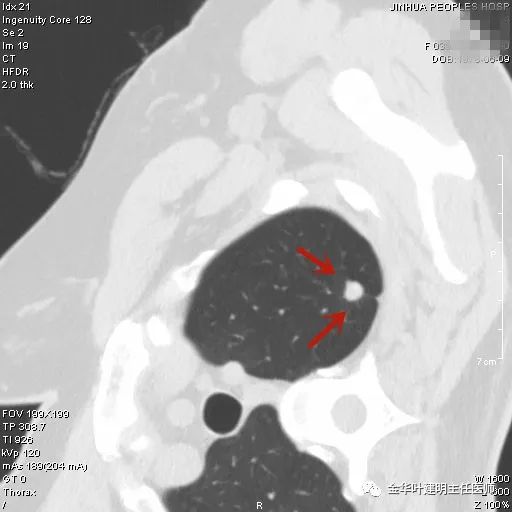

上图示浸润性腺癌典型表现。实性结节,有细毛刺征,有血管进入病灶,部分地方有浅分叶。